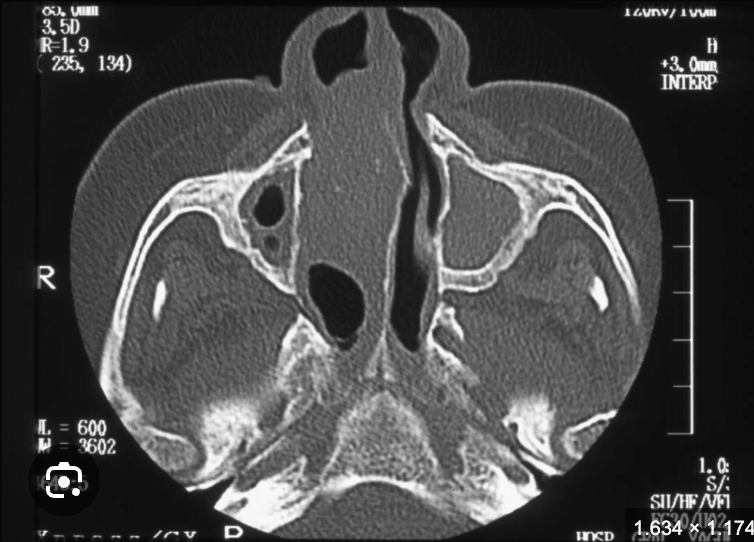

Imagen rinoescleroma